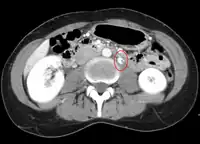

- Thrombosis in the left renal vein associated with dilation